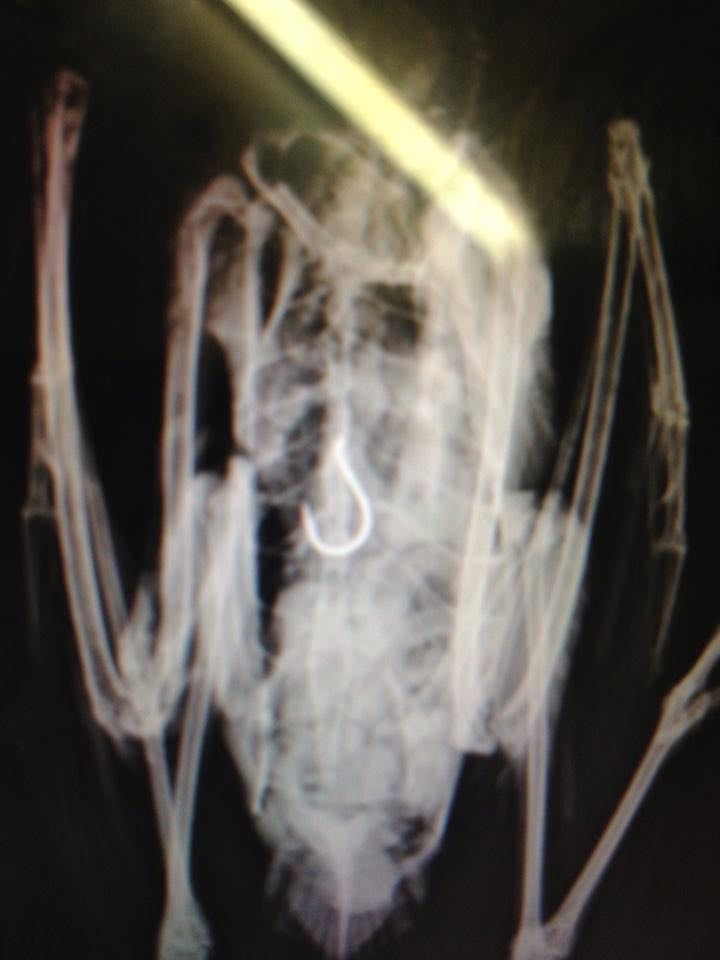

If you're fishing, make sure you take all your fishing hooks and line with you. Many of our sea-birds get horribly entangled in fishing line or swallow fish-hooks that have not been properly discarded.

Radiography of a sea-gull that has ingested a discarded fish-hook.